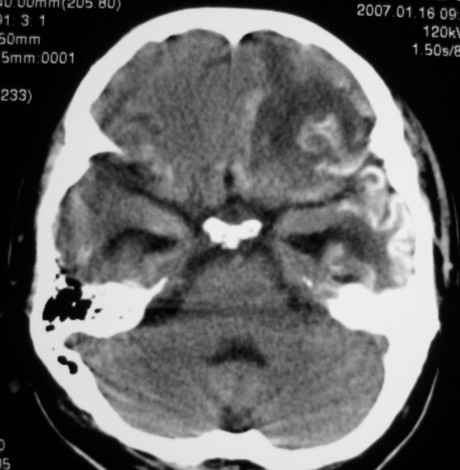

标题: CT9218:男性,50岁,脑出血术后复查,两次片相隔半月,请分 [打印本页]

标题: CT9218:男性,50岁,脑出血术后复查,两次片相隔半月,请分

第一次ct片脑出血术后,出血吸收期。第二次ct 片左颞顶枕部及右颞顶部有脑回样高密度影。考虑珠网膜下腔出血。脑出血术后改变,脑出血恢复期 并脑积水。

两次的片都有,第二次比第一次的明显